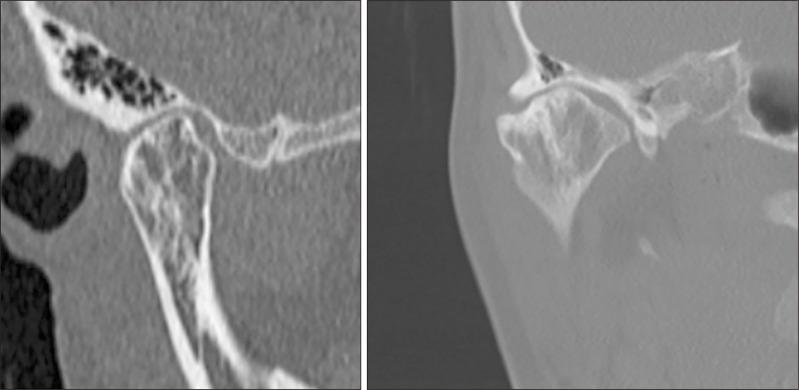

In patients with unilateral mandibular condyle hyperplasia, whether to perform condylectomy and orthognathic surgical procedures at the same time or orthognathic surgery in two stages for remains controversial. Reported here is a case of facial asymmetry with mandibular condyle hyperplasia, for which condylectomy and orthognathic surgery procedures were performed at the same time. A 28-year-old woman was presented to our department with chief complaints of left deviation of the mandible and right temporomandibular joint (TMJ) noise. Findings obtained in several imaging examinations led to a diagnosis of facial asymmetry associated with right mandibular condyle hyperplasia. Following 3 months of preoperative orthodontic treatment, in October 2018 under general anesthesia the patient underwent a right mandibular condylectomy, Le Fort I osteotomy, right mandibular sagittal split ramus osteotomy, and left mandibular inverted L ramus osteotomy. In examinations up to 3 years after surgery, good results were noted. For this case of severe facial asymmetry with mandibular condyle hyperplasia, early surgery and condylectomy were performed simultaneously to significantly shorten the total treatment time. The effectiveness of a surgery-early approach was confirmed by no postoperative findings indicating abnormalities in the TMJ or retroversion.

对于单侧下颌髁突增生的患者,是同期进行髁突切除术和正颌外科手术,还是分两阶段进行正颌手术,目前仍存在争议。本文报道了一例下颌髁突增生导致面部不对称的病例,该病例同期进行了髁突切除术和正颌外科手术。一名28岁女性因下颌向左偏斜及右侧颞下颌关节(TMJ)弹响为主诉前来我院就诊。多项影像学检查结果诊断为与右侧下颌髁突增生相关的面部不对称。经过3个月的术前正畸治疗后,2018年10月患者在全身麻醉下接受了右侧下颌髁突切除术、Le Fort I型截骨术、右侧下颌矢状劈开升支截骨术和左侧下颌倒L形升支截骨术。在术后长达3年的检查中,结果良好。对于这例严重的下颌髁突增生导致面部不对称的病例,早期进行手术并同期进行髁突切除术,显著缩短了总治疗时间。术后未发现TMJ异常或后倾等异常情况,证实了早期手术方法的有效性。